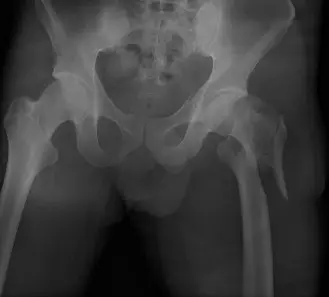

- هي الفحص الأول والأكثر أهمية. تؤخذ صور للورك والحوض من زوايا مختلفة (أمامية خلفية وجانبية).

- تُظهر بوضوح خط الكسر في المنطقة بين المدورين.

- تُبين مدى تفتت العظم (Comminution)، خاصة في القشرة الخلفية الإنسية (Medial Posterior Cortex) والمدور الصغير.

- تُحدد ما إذا كان هناك تحرك للجزء العلوي من عظم الفخذ باتجاه الأعلى (Proximal Migration) أو دوران خارجي، وهي علامات تدل على نمط كسر غير مستقر.

- تُساعد في تصنيف الكسر (مثل تصنيف AO/OTA أو Evans-Jensen) لتوجيه القرار الجراحي.

(صورة توضيحية لكسر عظم الفخذ بين المدورين، تُظهر التفتت النموذجي والتحرك.)